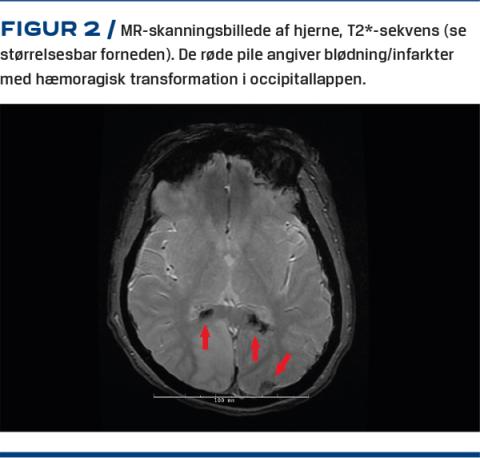

På klinisk og morfologisk mistanke om akut promyelocytleukæmi (APL) blev der initieret akut behandling med højdosis A-vitaminsyre, trombocyttransfusion, bredspektret antibiotika, aggressiv væsketerapi, rasburikase, dexametason og cytoreduktion (hydroxyurea). Patienten blev overflyttet til et intensivafsnit til overvågning samt korrektion af elektrolytniveau og optimering af koagulationsstatus. En MR-skanning af cerebrum (Figur 2) viste multiple friske infarkter med hæmoragisk transformation i bl.a. regio frontalis dxt. i gyrus præfrontalis og bilateralt occipitalt samt et laminært subduralt hæmatom. Ved en knoglemarvsbiopsi inkl. fluorescens in situ-hybridisering bekræftedes diagnosen APL. Patienten overlevede den første kritiske fase, og en knoglemarvsbiopsi fire uger efter debut viste morfologisk og cytogenetisk komplet remission.